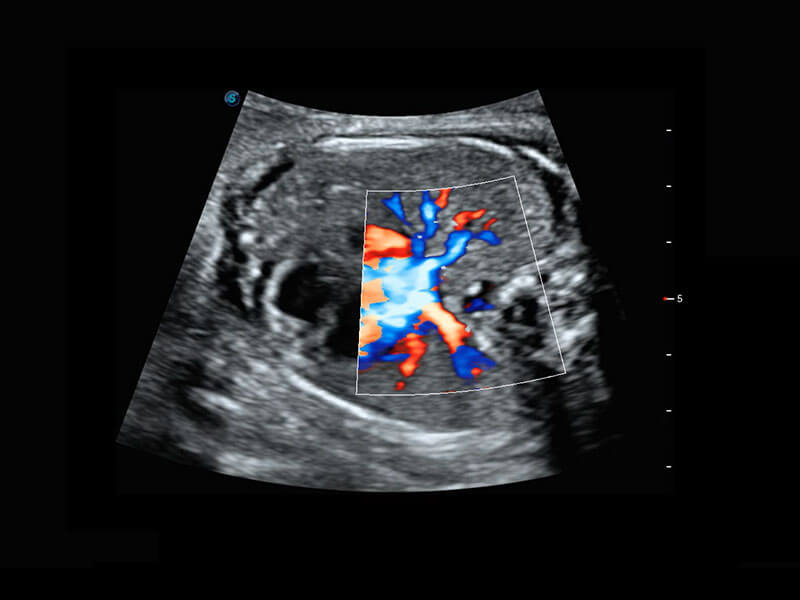

P60搭載一系列胎兒心臟成像技術(shù),實(shí)現(xiàn)精細(xì)的胎兒心臟評(píng)估。

四腔切面

四腔心血流

右室雙出口

胎心容積成像